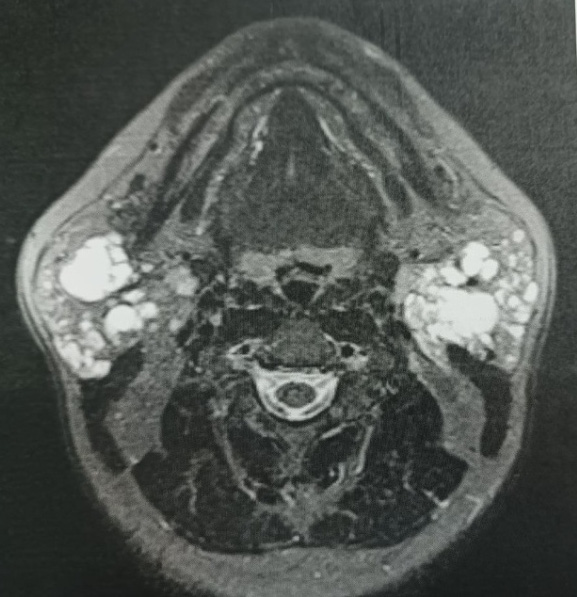

Кожные покровы лица в цвете не изменены, инфильтрация тканей отсутствует. Околоушные слюнные железы справа и слева увеличены в размерах: слева до 6,0´8,0 см, и справа: до 7,0´6,0 см, визуально не контурируют, при пальпации эластической консистенции, безболезненные, с бугристой поверхностью. В задненижнем отделе околоушно-жевательной области слева определяется участок уплотнения, размером 2,0´2,0 см. Открывание рта не нарушено. Органы полости рта без анатомических и функциональных отклонений. Признаков нарушения саливации не выявлено. Проведена оценка результатов инструментального исследования. Заключение УЗИ от 24.06.2024: множественные жидкостные образования в проекции околоушных слюнных желез. Цитологическое исследование от 08.08.2024: бесструктурные массы, клеточных элементов не выявлено. МРТ от 23.07.2024: картина увеличения размеров околоушных слюнных желез

с наличием множественных кистозных включений (рис. 2).

Рис. 2. Аксиальный срез МРТ пациента С. Околоушные железы справа и слева увеличены в объеме, в их структуре визуализируются множественные кистозные включения